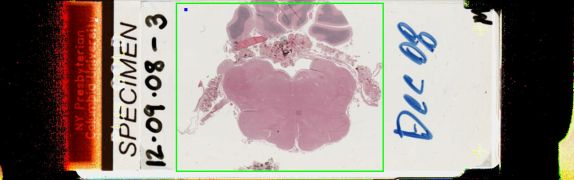

12/9/2008 Case 3: Anaplastic (WHO grade III) ependymoma

The patient is a 66 year old woman with intradural, extramedullary spinal masses, with evidence of thoracic spinal cord compression.  She underwent resection of the thoracic lesion, followed in five days by resection of a separate cervical lesion.  The submitted material was from the cervical resection, which had the same histology as the thoracic lesion.

Frozen section showed a tumor with pseudorosettes and uniform nuclei, which was well-demarcated and markedly hypercellular in some areas.  There were also solid areas and some papillary areas.  There were mitoses and anaplastic nuclei.  The differential diagnosis included extra-axial ependymoma, possibly tanicytic, or anaplastic, and meningioma.

Work-up revealed a MIB1 which was low in some areas and up to 40% in other areas, consistent with two parts to the tumor.  The cellular portion had a GFAP that was somewhat positive and a dot-like pattern on EMA staining, and was thought to be ependymal.  The transthyretin staining was thought to be a red herring.

The second resection (cervical mass) showed the same histology, and the tumor made a ventricular lining at the edge, together with some ciliated cells.

The diagnosis was Anaplastic ependymoma, WHO II, with zones of lower grade ependymoma.

Slide Image:

view high resolution slide image